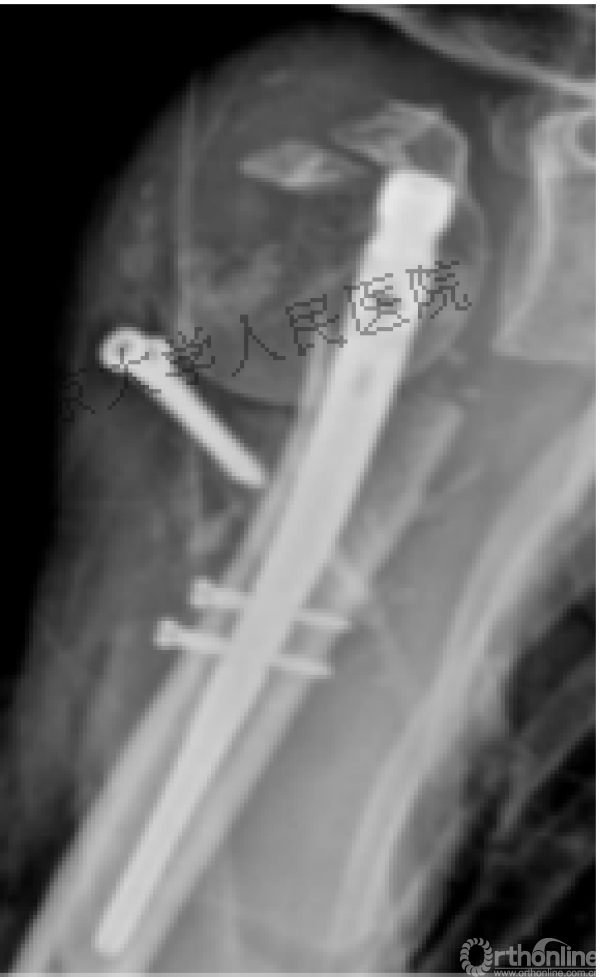

术后复位丢失,肱骨头内翻畸形。

能否该偏心固定(钢板)为髓内固定,增加力臂?

此时对比髓内钉是不是有很大优势?